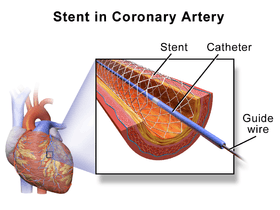

| Coronary stents are placed during a percutaneous coronary intervention, also known as angioplasty. The most common use for coronary stents is in the coronary arteries, into which a bare-metal stent, a drug-eluting stent, a bioabsorbable stent, a dual-therapy stent (combination of both drug and bioengineered stent), or occasionally a covered stent is inserted. |  A coronary stent |